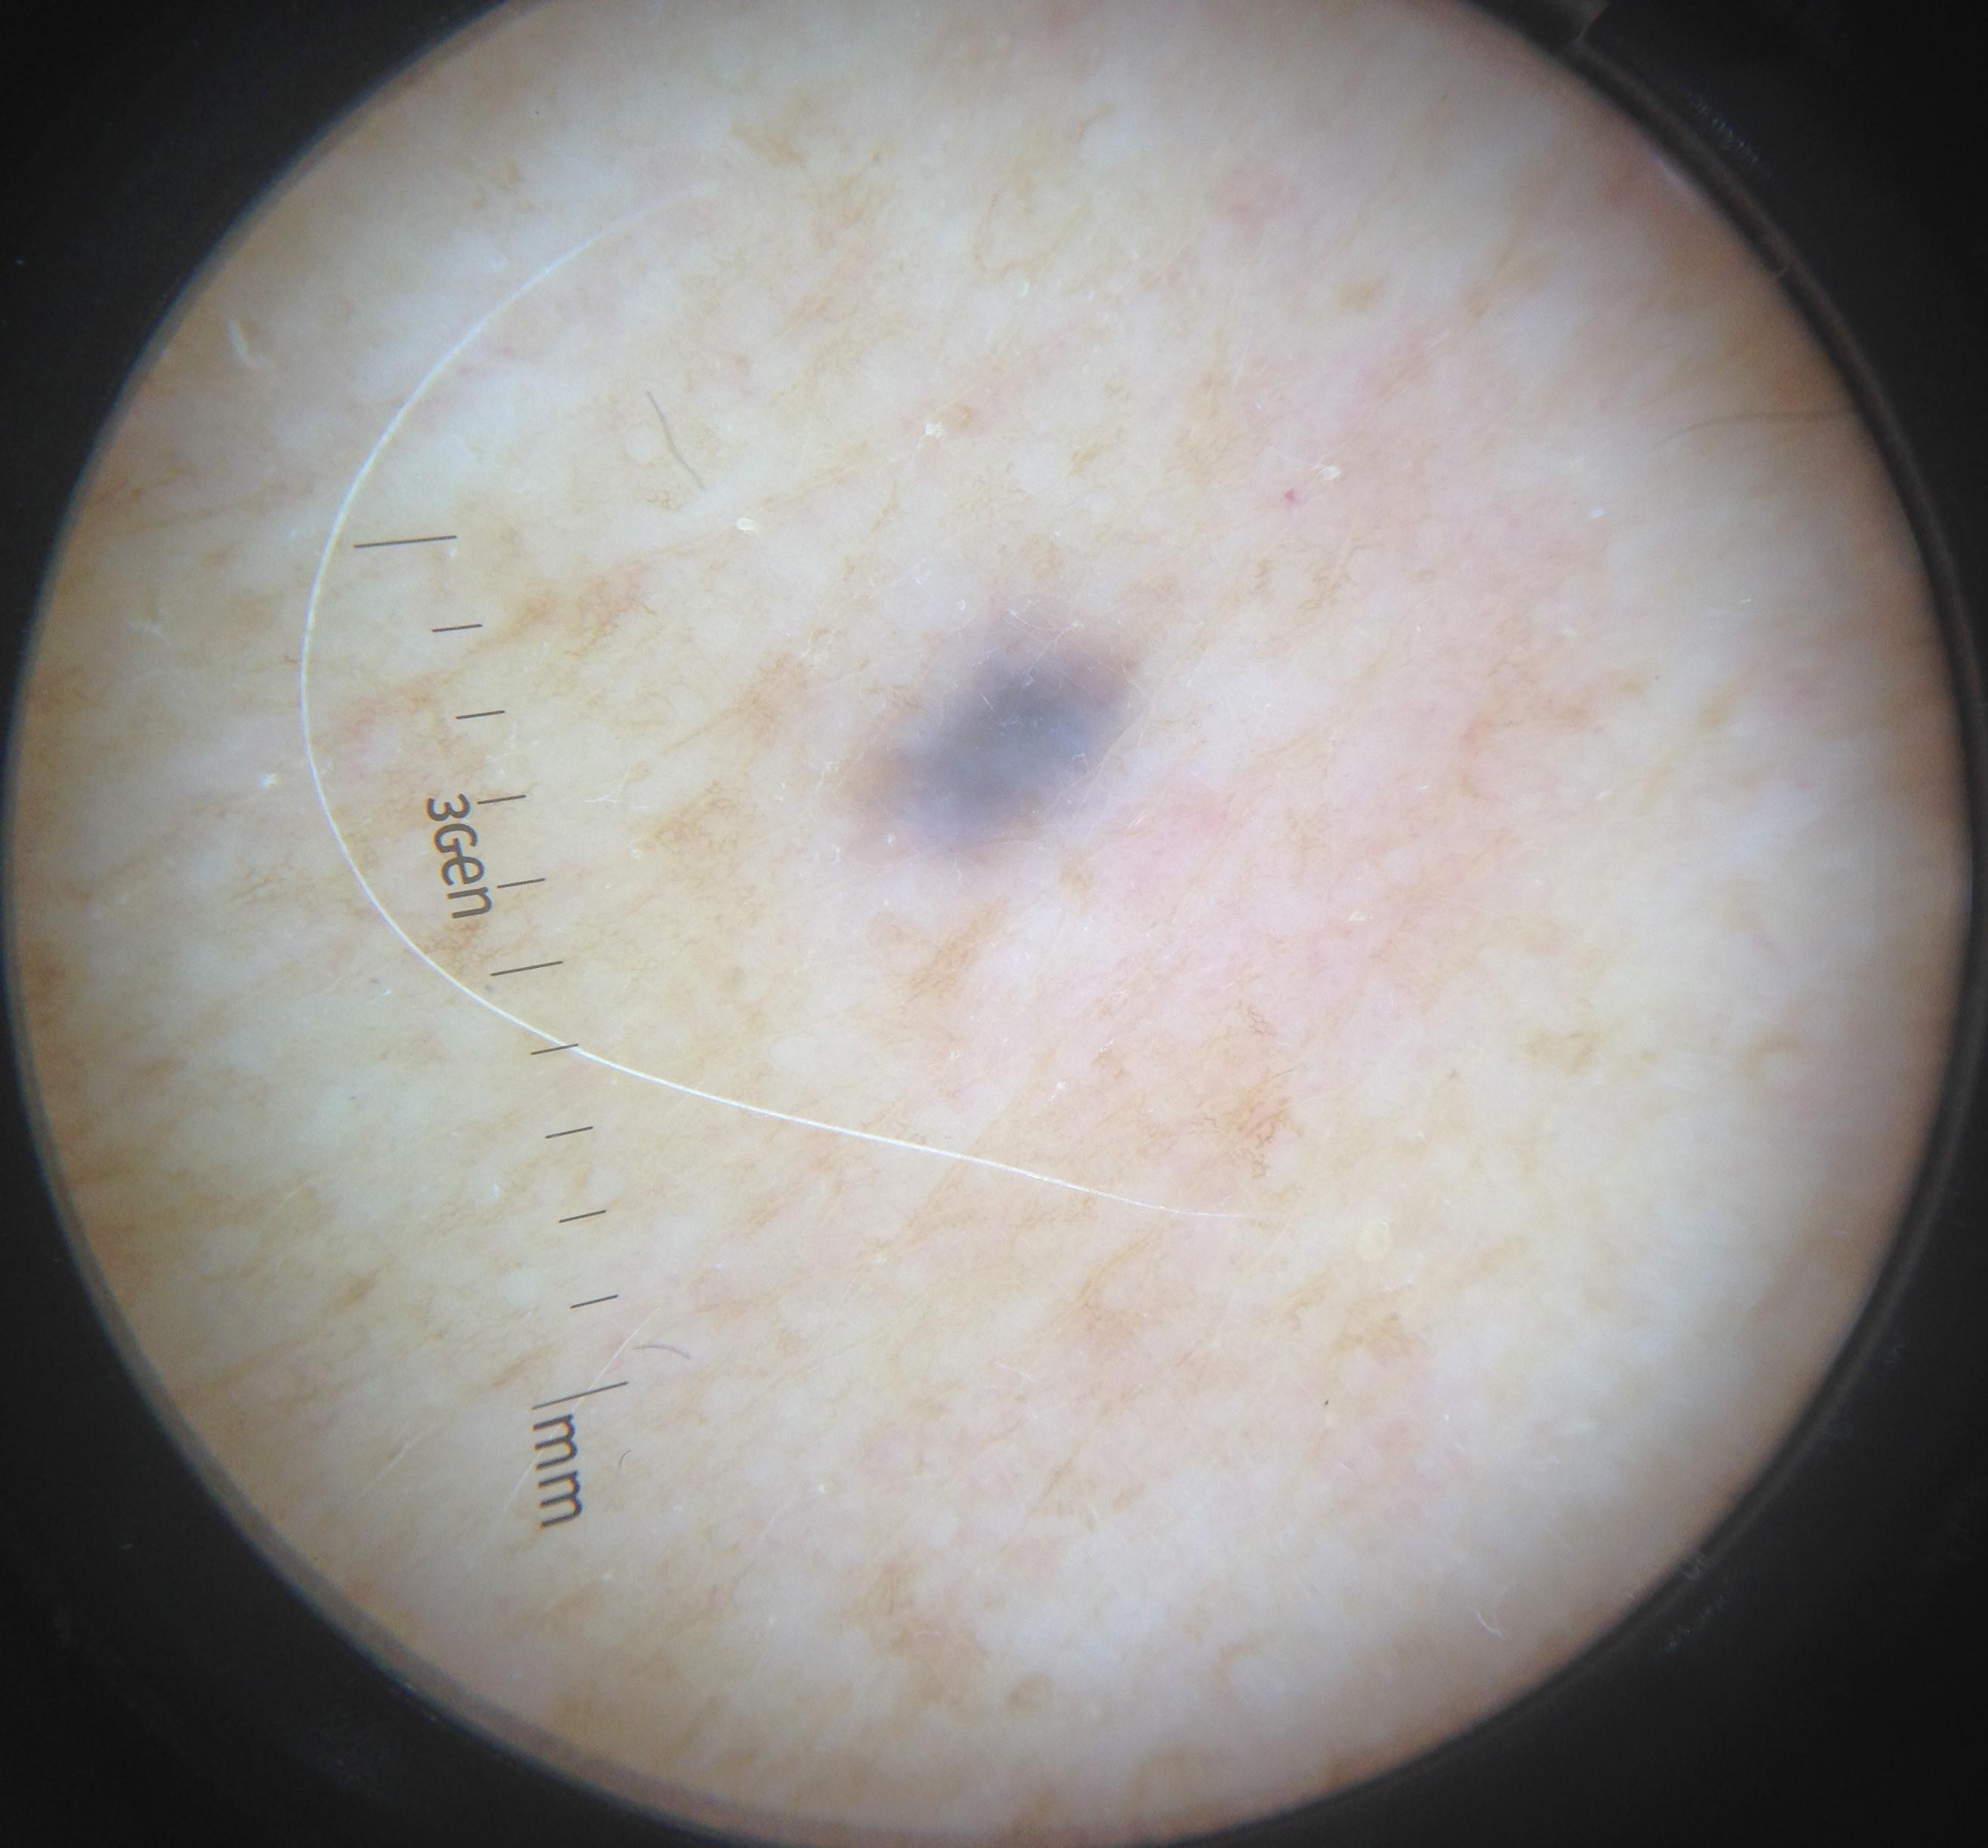

Skin lesion datasets provide essential information for understanding various skin conditions and developing effective diagnostic tools. They aid the artificial intelligence-based early detection of skin cancer, facilitate treatment planning, and contribute to medical education and research. Published large datasets have partially coverage the subclassifications of the skin lesions. This limitation highlights the need for more expansive and varied datasets to reduce false predictions and help improve the failure analysis for skin lesions. This study presents a diverse dataset comprising 12,345 dermatoscopic images with 40 subclasses of skin lesions, collected in Turkiye, which comprises different skin types in the transition zone between Europe and Asia. Each subgroup contains high-resolution images and expert annotations, providing a strong and reliable basis for future research. The detailed analysis of each subgroup provided in this study facilitates targeted research endeavors and enhances the depth of understanding regarding the skin lesions. This dataset distinguishes itself through a diverse structure with its 5 super classes, 15 main classes, 40 subclasses and 12,345 high-resolution dermatoscopic images.